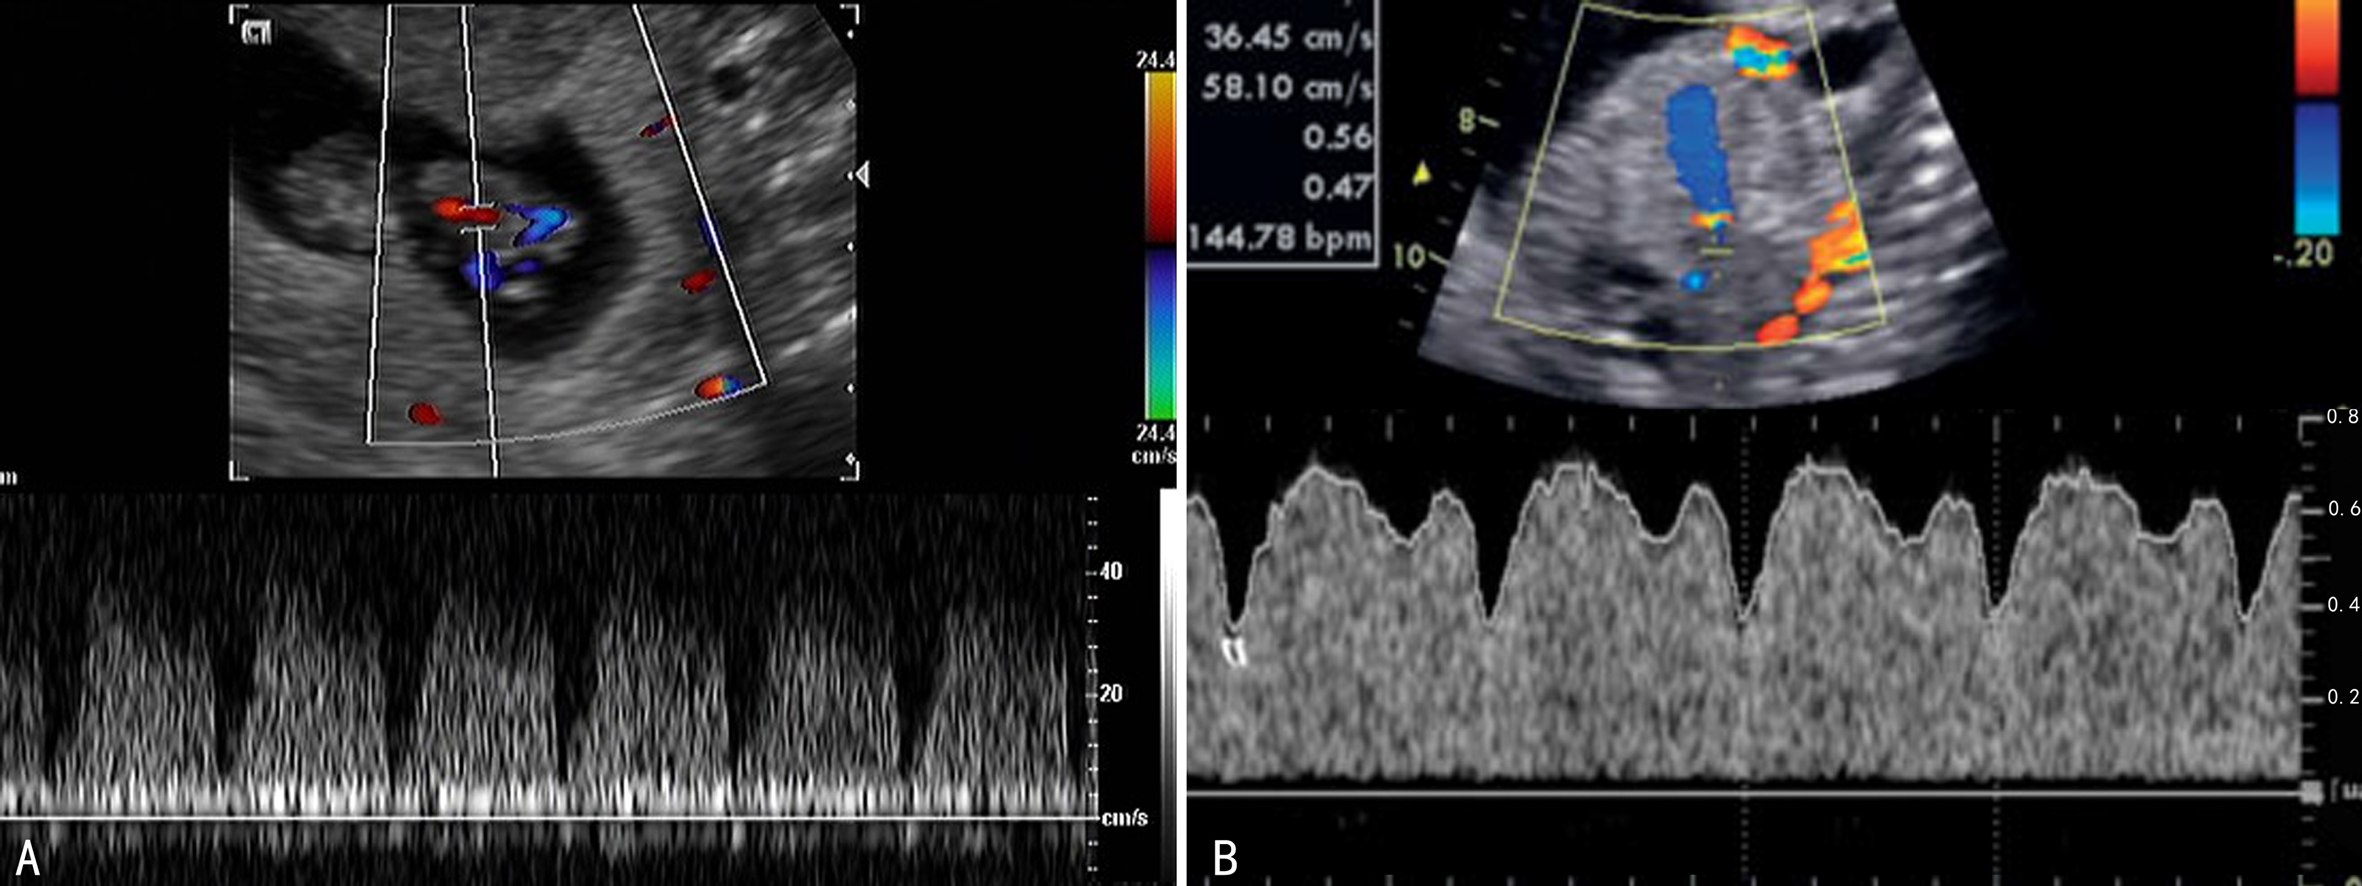

(一)降主动脉及腹主动脉

降主动脉检查的标志点位于主动脉弓动脉导管汇入处以下至膈肌动脉裂孔处。孕11周以前降主动脉无舒张期血流,显示为单峰血流,15周后出现舒张期血流,20周时舒张期血流明显增加,PI下降。FGR时降主动脉血流峰值速度降低,降主动脉舒张期血流消失。腹主动脉的显示、检测部位及血流速度曲线与降主动脉相似。

(三)腔静脉

包括上腔静脉和下腔静脉。检查可以在胎儿右心房后方显示方向相反的向心的血流,频谱多普勒检查时取样点以近右心房入口为标志点。正常上腔静脉和下腔静脉内血流频谱相似,均显示为三相波,首先是右心房收缩所致的反向A峰,其后是由右心脏收缩期引起的向心性V峰和心脏舒张早期向心性E峰。下腔静脉压力升高时可引起V/E比值减少。